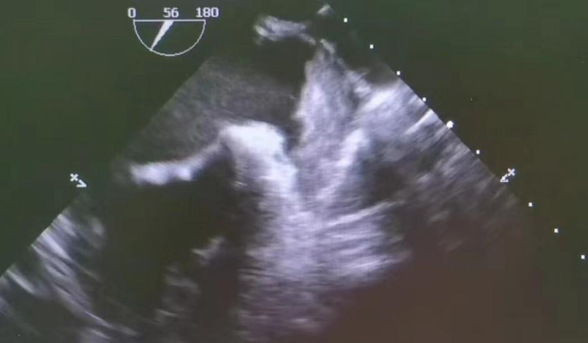

张某,女,38岁,无明显诱因的反复出现偏头痛,多次于外院就诊,予药物治疗后症状无明显缓解,遂来我院神经内科就诊。考虑张女士症状明显,于是进一步完善食道超声检查,结果得到超声图像印证,张女士患有卵圆孔未闭。为避免患者因长时间卵圆孔未闭而易患血栓,血栓脱落致脑梗的几率,建议患者进行卵圆孔封堵手术。

超声科进行经食道超声心动图检查